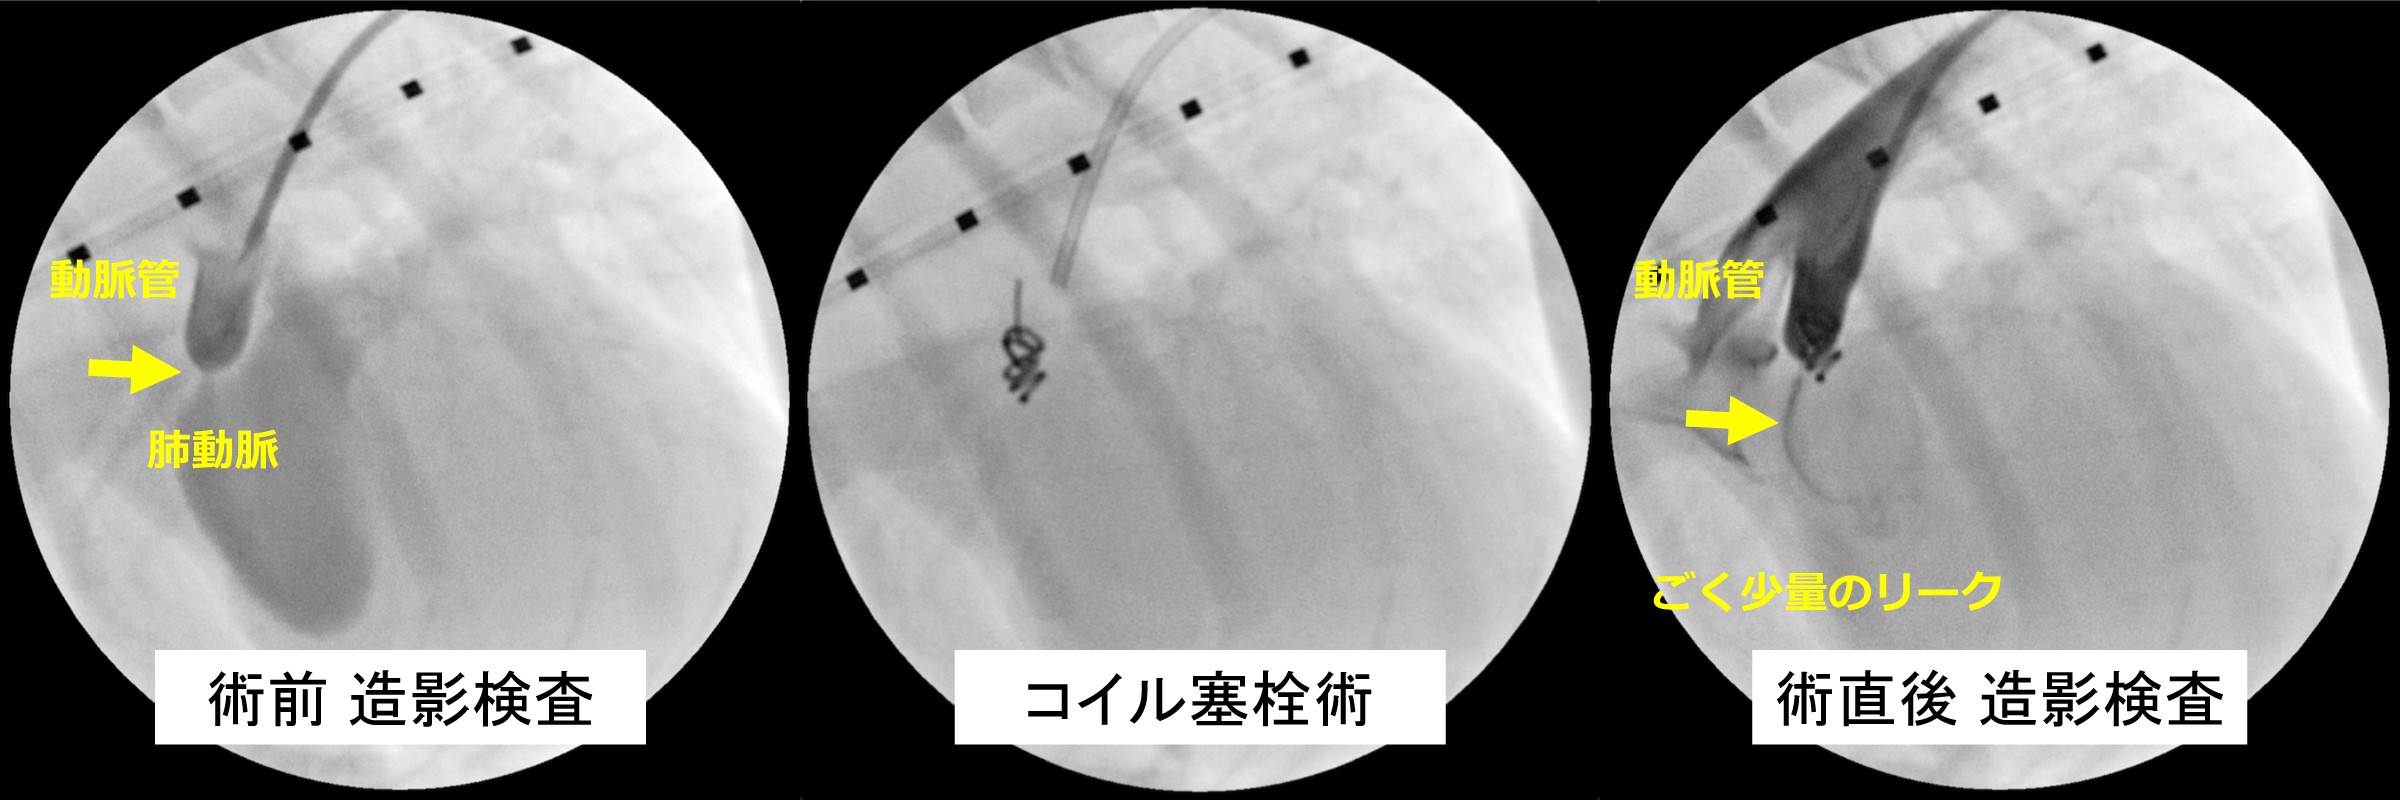

術後合併症なく、数日後には、完全閉塞となった